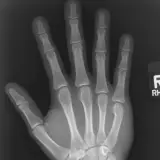

Over 2,100 interactive radiology cases, curated by radiologists for your level of training. Scroll, window, and view cases full screen โ€” just like on PACS. Click linked findings in each writeup to jump straight to them on the image. Cases include sample reports, a focused discussion section, original illustrations, and videos.

PACS์—์„œ ๊ธฐ๋Œ€ํ•  ์ˆ˜ ์žˆ๋Š” ๋ชจ๋“  ๋„๊ตฌ๋ฅผ ๊ฐ–์ถ˜ ์™„์ „ํ•œ ์ธํ„ฐ๋ž™ํ‹ฐ๋ธŒ ์ฆ๋ก€ — ์Šคํฌ๋กค, ์œˆ๋„์šฐ ์กฐ์ ˆ, ํ™•๋Œ€/์ถ•์†Œ, ํŒจ๋‹, ๊ณ„์ธก, ROI, ์ „์ฒด ํ™”๋ฉด ๋ชจ๋“œ๊นŒ์ง€ ์ง€์›ํ•ฉ๋‹ˆ๋‹ค.

์‹ค์ œ PACS ์›Œํฌ์Šคํ…Œ์ด์…˜์ฒ˜๋Ÿผ ์Šคํฌ๋กค, ํŒจ๋‹, ์œˆ๋„์šฐ ์กฐ์ ˆ, ํ™•๋Œ€/์ถ•์†Œ๊ฐ€ ๊ฐ€๋Šฅํ•ฉ๋‹ˆ๋‹ค